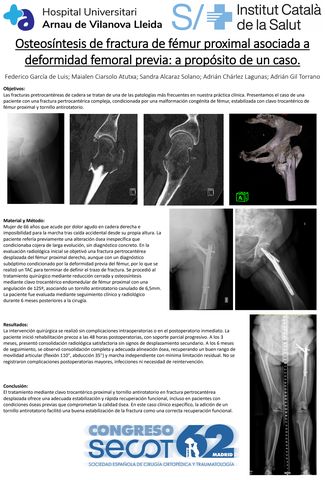

Osteosíntesis de fractura de fémur proximal asociada a deformidad femoral previa: a propósito de un caso.

FEDERICO GARCIA DE LUIS, MAIALEN CIARSOLO ATUTXA, SANDRA ALCARAZ SOLANO, ADRIÁN GIL TORRANO, ADRIAN CHARLEZ LAGUNAS